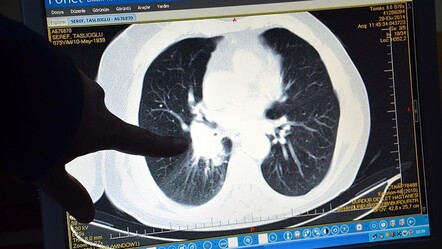

Boyunda ana damarların geçtiği yerlerin olduğuna dikkat çeken Şen, ani hareketler sırasında o damarların zarar görüp beyine giden kan akışının azabileceğini vurgulayarak şunları söyledi:

“Berber koltuğunda oturduğunuzda boynunuzu kütletmeyin. Birçok kişiye olmaz ama bir kişiye olduğunda boyundan aşağı felç kalabilirsiniz. Ayrıca, genelde toplumda sırt ağrısı çekenler uzanıp üzerine 70-80 kilogram ağırlığındaki insanları alıp yürütüyorlar. Sizde kemik erimesi olabilir, öyle bir ağırlık çıktığı zaman omurganızda kırıklar gelişebilir. Bilimin ışığında ilerleyip, bu tarz hareketleri yapmayalım.”